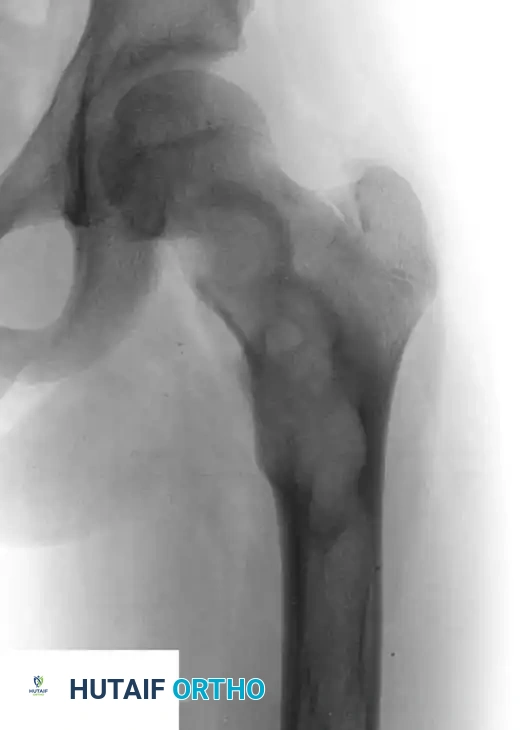

The radiographic signature of fibrous dysplasia is a radiolucent, expansile lesion with a characteristic granular, "ground-glass" matrix.

Fig. 20-10 A and B: Left hip of a 12-year-old girl demonstrating the classic ground-glass appearance and expansile nature of fibrous dysplasia.